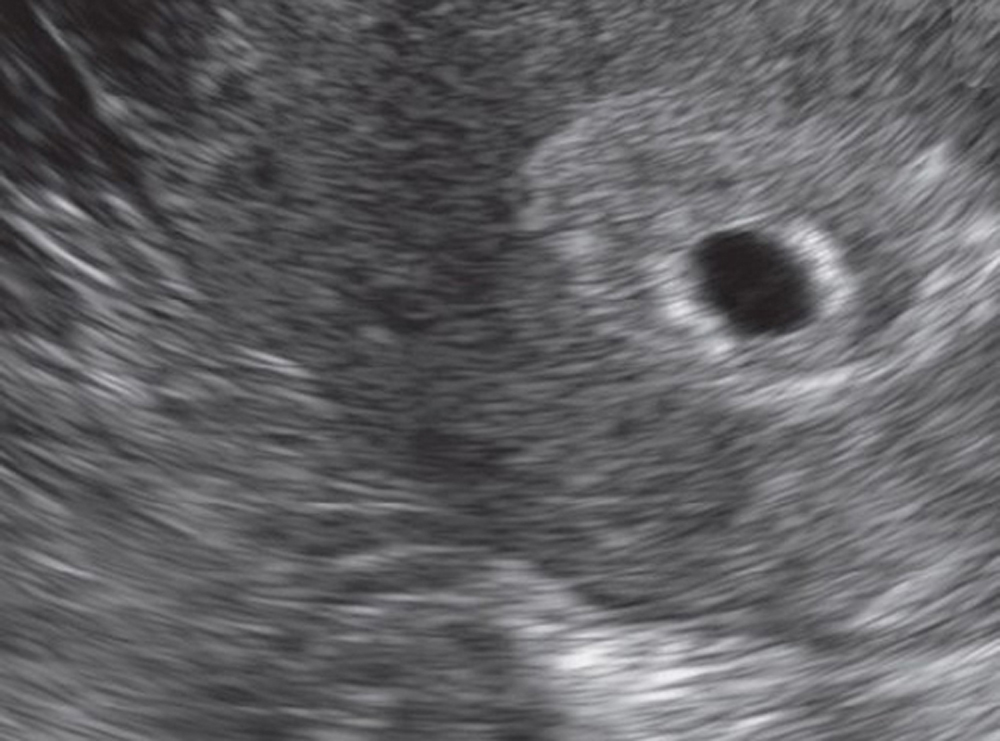

Bewertung der Blastozyste) Wann Einnistung? Forum Unterstützter Kiwu Einnistung Wann Abgeschlossen Dein körper beginnt erst dann mit der produktion von hcg, wenn die einnistung abgeschlossen ist — also höchstwahrscheinlich 8 bis 10 tage nach der empfängnis. Wenn du einen zyklus von 28 tagen hast, dann wird die einnistung wahrscheinlich am 19. Die einnistung ist ein komplexer prozess, der mehrere tage dauert. Für gewöhnlich kommt es direkt am tag des eisprungs zur. Einnistung Wann Abgeschlossen.